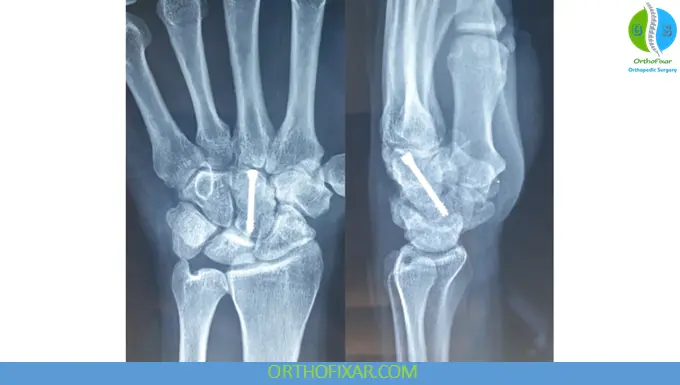

Prompt anatomical reduction is critical to minimize the risk of complications. Treatment options include:

- Closed reduction, if achievable

- Open reduction and internal fixation (ORIF) when closed methods fail

Internal fixation is typically performed using:

- Kirschner wires (K-wires)

- Lag screws

The primary goal is restoration of normal carpal alignment and vascular integrity.